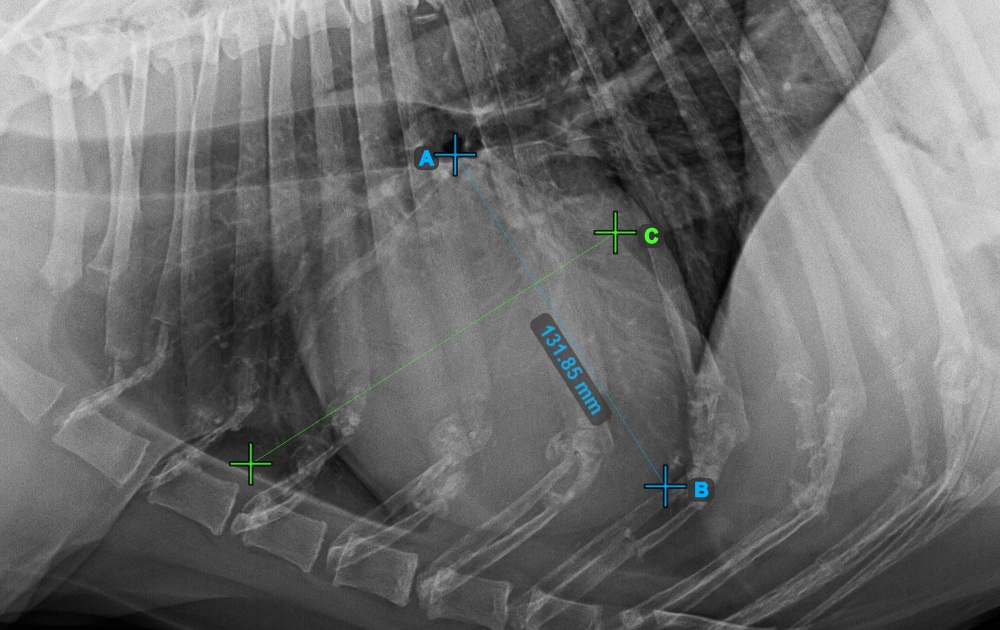

Fejezze be a szív hosszanti tengelyét az Apex pont megjelölésével, a szív alsó részéhez közel.

Az alábbi kép az Apex pont tipikus elhelyezkedését mutatja.

Folytassa a mérést a szív rövid tengelyének legszélesebb jobb (feji) pontjának megjelölésével.

Az alábbi kép a szív rövid tengelyének „legcranialisabb” pontjának tipikus elhelyezkedését szemlélteti